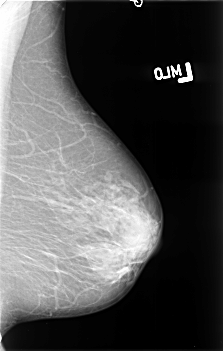

B_3395_1.LEFT_MLO

LEFT_MLO LINES 4552 PIXELS_PER_LINE 2888 BITS_PER_PIXEL 12 RESOLUTION 50 NON_OVERLAY